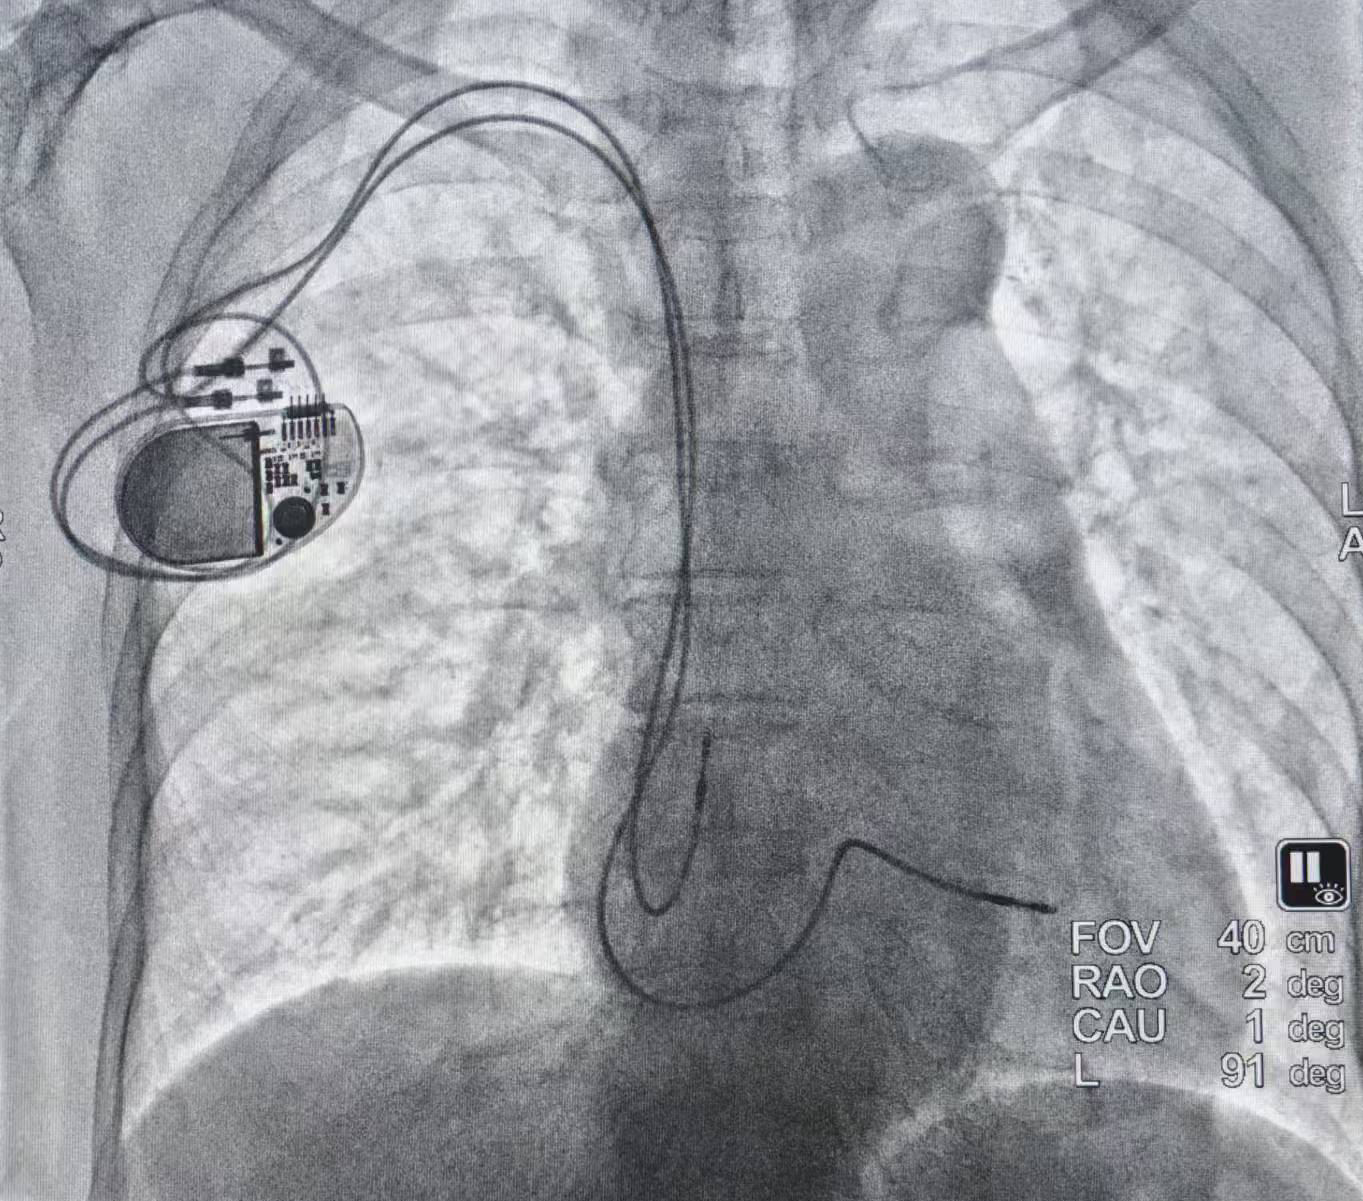

面对这份沉甸甸的信任与高难度的手术挑战,由刘启明教授团队的核心成员陈明鲜副主任主刀,为患者实施了右侧锁骨下双腔起搏器植入术。整台手术顺利圆满,术后起搏参数测试理想。这一成功,不仅标志着患者重获健康心跳,更一举驱散了萦绕在他心头长达二十年的阴霾。